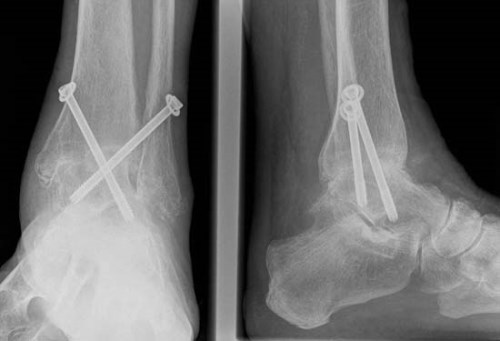

Артодез на этом суставе могут проводить как под общей, так и под спинальной анестезией. Для сращивания могут использовать специальные шурупы, винты, пластины, стержни, костные трансплантаты и другие медицинские приспособления для фиксации.

Во время операции пораженный сустав удаляется и обеспечивается сращивание двух костей, или создается искусственный костный анкилоз.

В процессе хрящевые поверхности таранной и большеберцовой костей удаляются, они сопоставляются и фиксируются. Человек перестает чувствовать боль, но также происходит компенсирование объема движений и нарушаются двигательные функции.